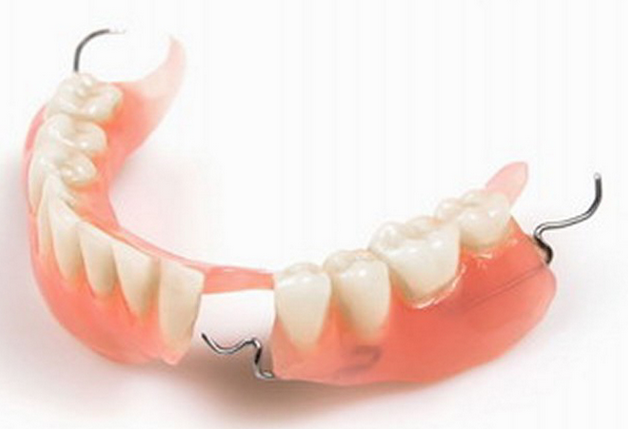

牙齿缺失后的修复方法有三种:

(2)活动义齿:利用剩余天然牙或粘膜作为支持,通过卡环固定在剩余天然牙上,同时利用基托使义齿保持适当的位置行使咀嚼功能,可以自行摘戴的一种修复体。